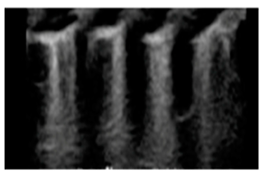

| Interstitial lung disease | “Confluent B-lines with discontinuity of the pleural line” | ![]() |